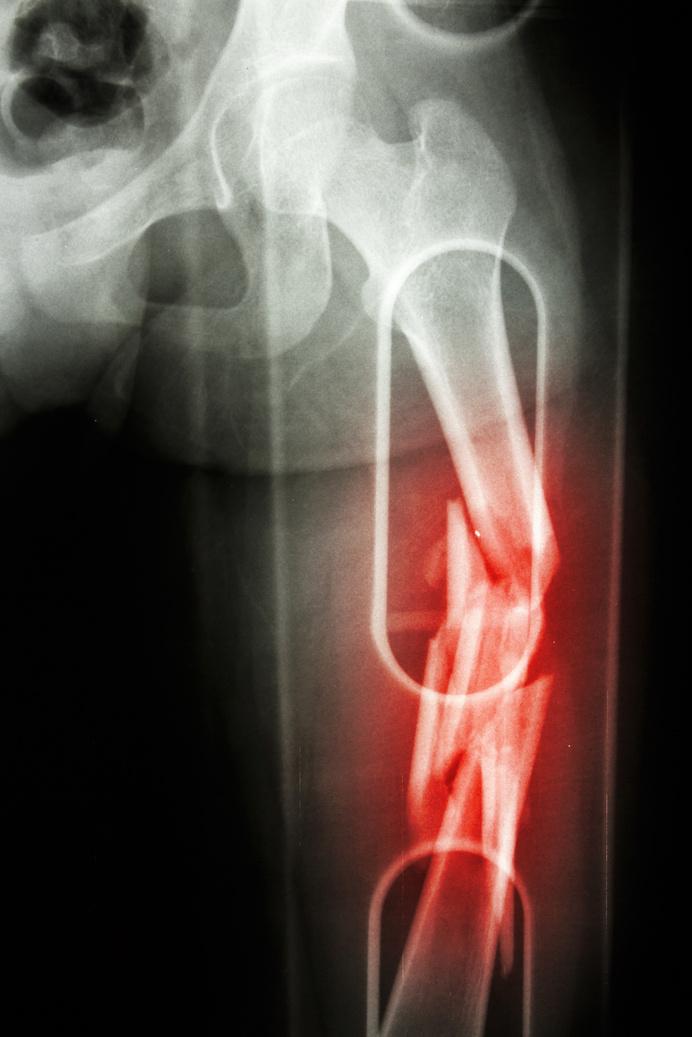

Patah tulang adalah keadaan hilangnya kontinuitas (kesinambungan) pada tulang atau keadaan tulang yang mengalami keretakan, pecah atau patah, kondisi ini tergolong cedera olahraga berat atau terparah, karena ketika tidak ditangani segera dan benar akan berdampak buruk pada pasien sehingga pasien bisa mengalami kecacatan permanen.

Berdasarkan continuitas patahan, fraktur dapat di golongkan menjadi dua yaitu :

1. Patah tulang tertutup, patahan tulang tidak sampai menembus permukaan kulit.

Patah tulang terbuka, patahan tulang melukai kulit dan tulang terlihat keluar

2. Fraktur terbuka fraktur tertutup

FRAKTUR

Terdapat prinsip utama yang perlu di perhatikan dalam melakukan pertolongan pertama fraktur yaitu, mempertahankan posisi, mencegah infeksi, dan mengatasi syok/fiksasi dengan pembidaian. Bidai (splint) merupakan alat yang digunakan untuk menstabilkan area cedera fraktur.

Pertolongan pertama yang dapat dilakukan pada kasus cedera patah tulang yaitu dengan :

Lakukan pengkajian pada pasien dengan cara melihat bagian tubuh yang sekiranya mengalami cedera, jika terjadi luka terbuka lakukan perawatan luka sebelum memasang bidai untuk mencegah infeksi

Pasang bidai (spalk atau splint) pada bagian tulang

yang patah, bidai digunakan jika korban mengalami nyeri lanjutan

Lakukan metode RICE ( Rest, Ice, Compression, Elevation)

Segera bawa korban ke rumah sakit untuk ditindak lanjuti